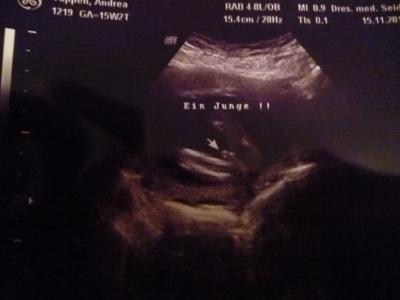

Ich noch mal, aus dem Mai -Bus! Ich hoffe ich nerve nicht. Aber es beschäftigt mich was! Hatte letzte Woche mein Outing: Ein Junge soll es werden. Das Problem ist, das sollte meine Tochter in der 14 und 16.SSW auch. Diesmal war der Artzt sich aber sehr sicher. Jetzt meine Frage bei wievielen lag er mit den Jungen Outing daneben und wann gab es ein Mädchen Outing bei euch?? Bin neugierig! Häng mal ein Bild von dem Outing dran!

Bild zu Outing Umfrage!!! - Forum für April - Mamis

Hallo Dana, da sieht man Penis mit Hodensack! Deutlicher gehts nicht :-) Das Problem ist, etwas zu sehen was nicht da ist (Mädchen) ist schwieriger als was zu sehen was DA ist (s.o.) Also das ist zu 100% ein Bub! Glückwunsch ! Liebe Grüße Hasi-Mama

Wir hatten unser Mädchenouting in der 20. SSW. Dieses Mal haben wir in der 16. SSW erfahren, dass es ein Junge wird. Dein Outing sieht wirklich sehr eindeutig aus.

Das Bild sieht doch für die 17. Woche sehr eindeutig aus! Meine Jungs Outings haben alle gestimmt.....kriegen jetzt unseren 5ten....gg Liebe Grüße Sonja